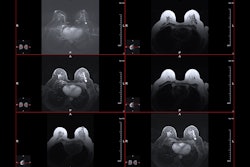

Apparent diffusion coefficient (ADC) measurements for benign and malignant BI-RADS category 4 or 5 lesions at MRI. (A, B) Benign BI-RADS category 4 lesion in a 55-year-old woman. (A) Dynamic contrast-enhanced MRI (DCE-MRI) scan shows a 12-mm, oval, circumscribed, homogeneous mass in the right posterior breast (arrow). (B) On the diffusion-weighted image, the lesion shows high diffusivity (arrow), with an ADC of 2.04 × 10-3 mm2/sec. Biopsy revealed benign fibroadenoma. (C, D) Malignant BI-RADS category 4 lesion in a 41-year-old woman. (C) DCE-MRI scan shows a 24-mm irregular, heterogeneous mass at the 3 o’clock position in the left breast (arrow). (D) On the diffusion-weighted image, the lesion demonstrates low diffusivity (arrow), with an ADC of 0.91 × 10-3 mm2/sec. Biopsy revealed invasive ductal carcinoma. All MRI scans are shown in the axial plane. (E) Box plot shows ADC measurements for 240 BI-RADS 4 and 5 lesions (63 malignant and 177 benign). Both prespecified optimal and conservative ADC cutoffs are indicated on the plot for reference: 1.53 × 10-3 mm2/sec (dashed line) and 1.68 × 10-3 mm2/sec (dotted line), respectively. All ADCs were calculated with maximum b value of 800 sec/mm2. The midline of each box shows the median value, and the box extends from first to third quartiles. The whiskers extend from the first and third quartiles to the smallest and largest values, respectively, if those values are within 1.5 times the IQR. If not, the length of the whiskers is limited to 1.5 times the IQR. Image courtesy of the RSNA.

The researchers tested the validity of point-of-care ADC measurements with the trial’s cutoff, with the goal of reducing unnecessary biopsies in lesions found by breast MRI. They included data from consecutively performed MRI exams from 2015 to 2019 at a single center. The exams showed biopsy-confirmed lesions at BI-RADS 4 or 5.

The team calculated sensitivity and biopsy reduction rates by applying the A6702 optimal (ADC, 1.53 × 10−3 mm2/sec) and alternate conservative (1.68 × 10−3 mm2/sec) cutoffs. The study included 240 breast lesions in 201 women with an average age of 49. Of the total lesions, 63 were deemed malignant while 177 were benign.